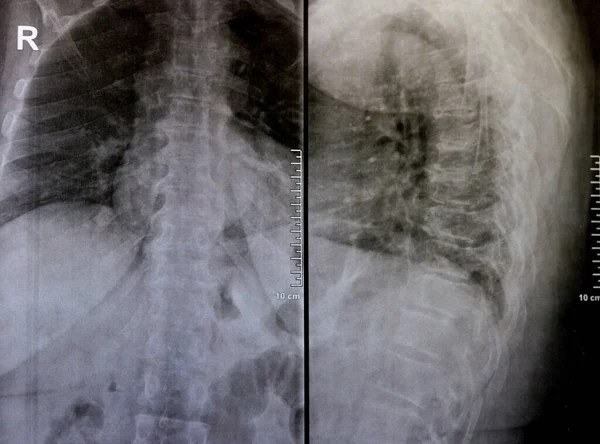

Sırt ve kereste omurgasının röntgen ışınları spondilotik değişimleri, sırt ve kereste dikenlerinin düzleştirilmesini, omurgalar arası disk alanlarının bozulmamış olduğunu, sırt ve kereste dikenlerinin Spondylosis 'inin bozulmamış olduğunu gösterir.